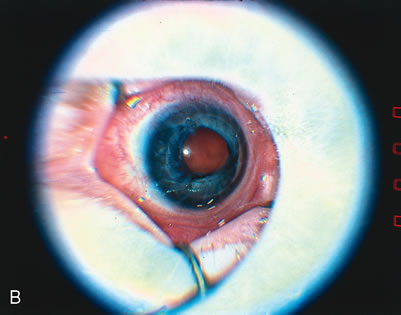

Threshold disease is defined as five contiguous or eight accumulated clock hours of stage 3 ROP with plus disease (Fig. 2). At threshold, the risk of 20/200 or worse final visual acuity is approximately 60% without treatment,10,11 and it is the level of disease at which treatment should be applied. When threshold disease is present, treatment should be performed within 72 hours of detection.13

Fig. 2. A. Clinical appearance of stage 3 ROP. This stage has growth of vessels with fibrous tissue out of the plane of the retina (extraretinal fibrovascular proliferation). B. Clinical appearance of plus disease. In the posterior pole, the retinal veins are engorged and tortuous. C. Two representative eyes that have reached threshold for treatment. The right eye (RE) has at least eight accumulative clock hours of stage 3 ROP. The left eye (LE) has at least five contiguous clock hours of stage 3 ROP. The thin line of ROP represents stage 1 or stage 2 disease, the broader sketched line signifies stage 3 disease. (From Cryotherapy for Retinopathy of Prematurity Cooperative Group: Multicenter trial of cryotherapy for retinopathy of prematurity. Preliminary results. Arch Ophthalmol 106:471–479, 1988. Copyright, Archives of Ophthalmology.)